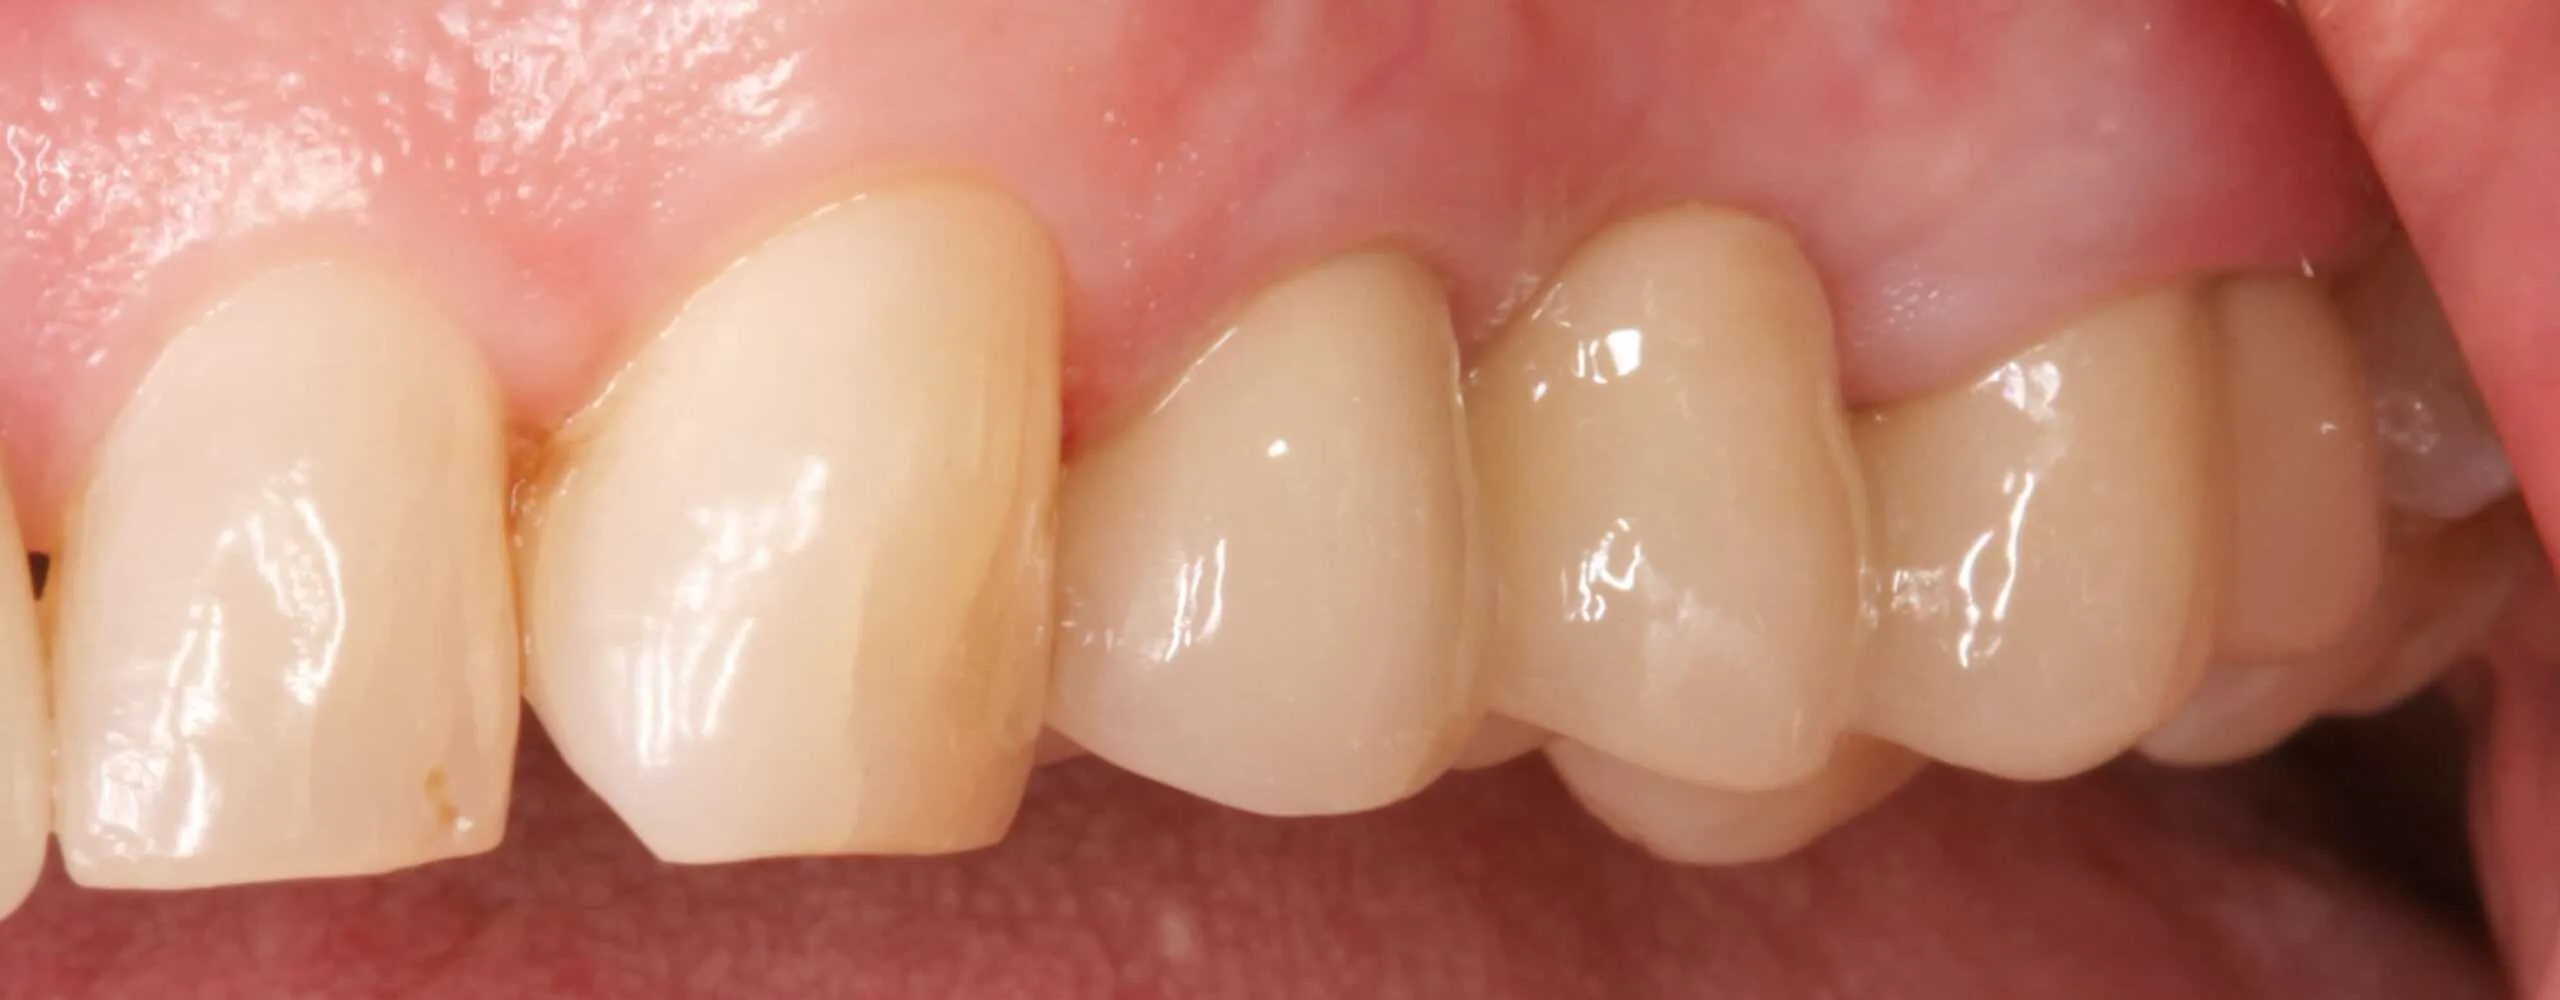

After:Â Revision crown and bridge therapy. Tooth #14 was carious and required root canal therapy and a build-up (foundation restoration) prior to definitive bridge therapy. Three-unit fixed partial denture (bridge), porcelain fused to gold, abutment teeth 12 and 14.